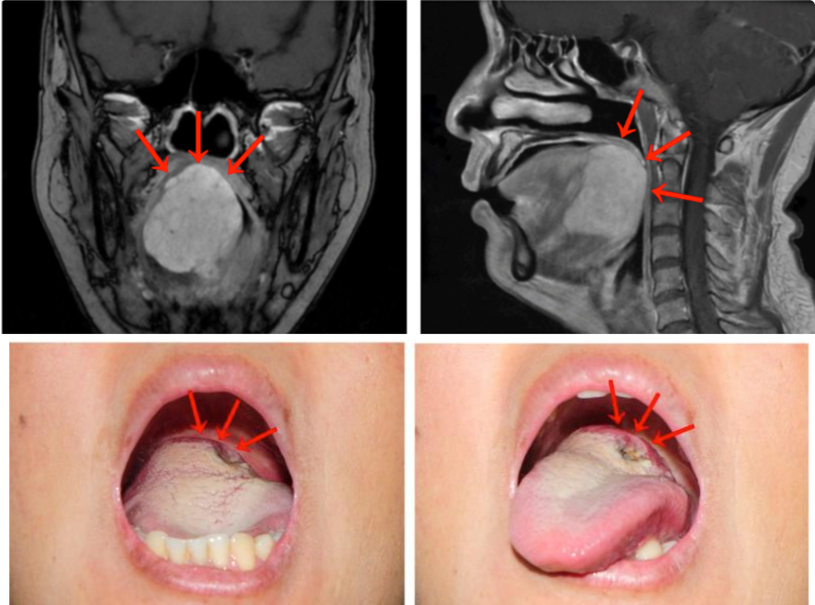

“刘女士的舌根部肿物达到5厘米,几乎占据整个舌根部并向口咽腔突出。中山大学肿瘤防治中心头颈外科门诊宋明主任医师表示,MRI检查提示舌根肿块巨大,范围约47毫米×46毫米×45毫米,向前侵犯部分舌体,向下侵犯部分口底肌群。活检病理诊断考虑为舌根腺样囊性癌。

面对刘女士舌根部肿物体积巨大的情况,医生陷入了两难:按传统的手术治疗方式,刘女士是需要接受开放性手术的,但这种术式需要将下唇及下颌骨裂开才能暴露并切除舌根肿瘤,对容貌会有一定的影响。

面对才40来岁的刘女士,医生建议她采用经口机器人手术。手术仅用时90分钟,出血量不足50毫升,成功将舌根肿瘤完整切除,并保证足够的安全边界,而且无需进行气管切开术。